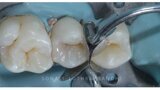

Management of proximal posterior lesions- A case report